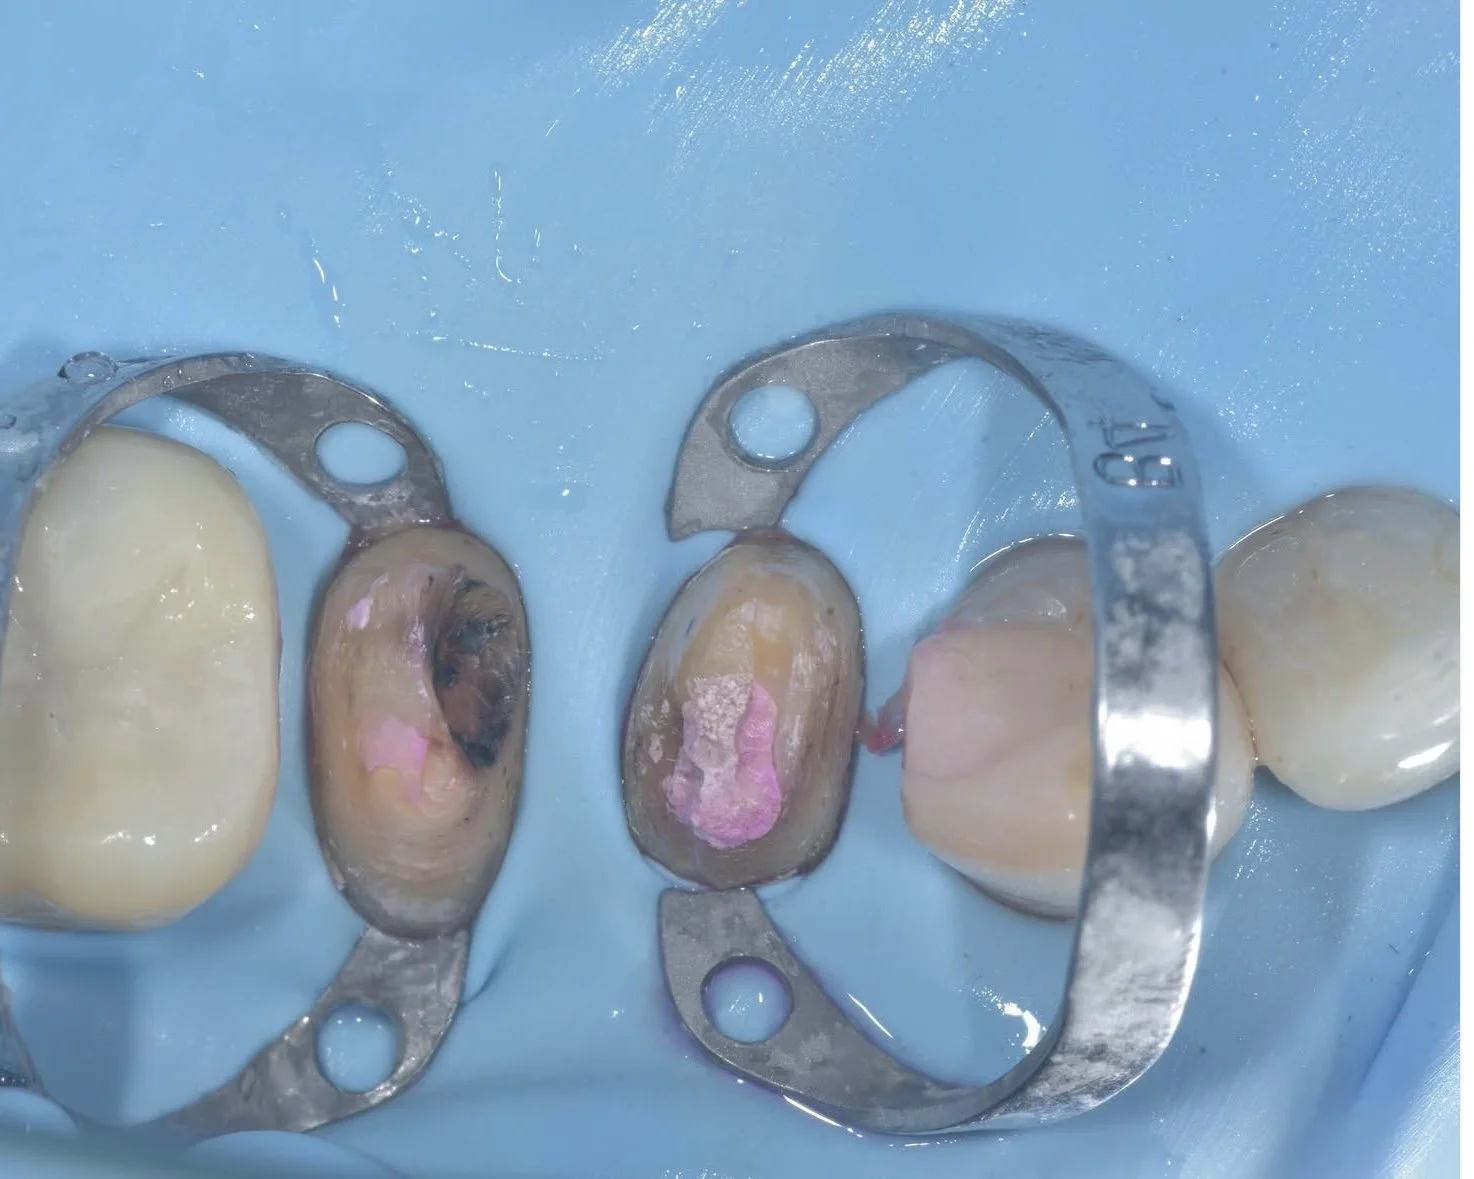

These photos of a traditional crown replacement and a biobase with a conserved biorim showing the difference in tooth structure between the preparations. Cases by Dr. Davey Alleman, DMD.

When treating large failing restorations, full coverage crows are no longer necessary. The advanced adhesive protocols of biomimetic dentistry allow critical tooth structure in the biorim to be conserved. Case by Dr. Davey Alleman, DMD.

Traditional crown preparations increase a tooth’s risk of fracture. Retreatment case by Dr. Davey Alleman, DMD.